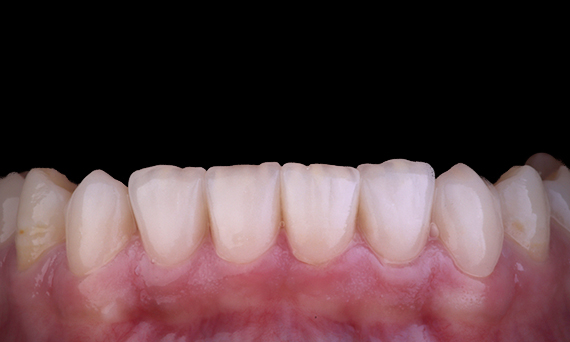

Oftmals sind sich die Patienten der Risse oder Hohlräume in ihren Zähnen nicht bewusst. Erst wenn ein Zahn schmerzt oder bricht, erkennen die meisten Patienten die Notwendigkeit, ihre Zähne kontrollieren zu lassen. Oft können wir Dinge wie Zahnbrüche vorhersehen, wenn bereits Risse vorhanden sind, eine starke Okklusion vorliegt oder ein früherer Zahnverlust auf einen Riss zurückzuführen ist. In diesem Fall hatte die Patientin einen asymptomatischen abgebrochenen oberen Prämolaren, der bei einer zahnärztlichen Routineuntersuchung entdeckt wurde. Der Patientin wurde das Foto des Zahns gezeigt und sie wurde über die Situation aufgeklärt, mit der Empfehlung, den Zahn restaurieren zu lassen. Die Patientin lehnte jedoch jede Behandlung ab, da der Zahn keine Beschwerden verursachte. 6 Monate später brach der Zahn, und nun konnte die Patientin die Behandlung nicht mehr aufschieben. Der Zahn wurde mittels CEREC mit einer Keramik-Kunststoff-Hybridkrone/einem Onlay in einer einzigen Sitzung restauriert.